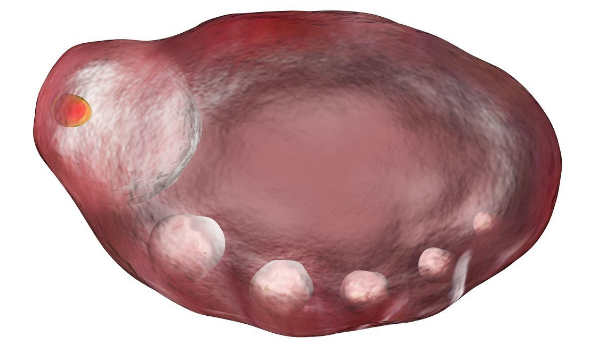

卵泡只有发育成熟才能诱发排卵,此时排出的卵子才会成熟健康且功能健全。而卵泡成熟的特征是呈圆形或椭圆形、直径达18-25mm、卵泡内呈无回声区、清亮纯净、边界清晰。若女性因卵巢疾病,如多囊卵巢综合症、下丘脑-垂体-卵巢轴功能异常或是内分泌紊乱等,导致卵泡发育不良,就会造成取卵数量降低,与前期看到的基础卵泡数量不同。

由于各种因素的影响,女性左右卵巢内出现的基础卵泡并不是所有的卵泡里都会有卵子存在。所以即便使用促排药物让基础卵泡发育成熟,也会因卵泡大小不一、发育程度不同,使不同卵泡里的卵子的脱离时间存在差异,导致部分卵泡里取不到卵子。由此导致获取的卵子数目与基础卵泡的数量不同。